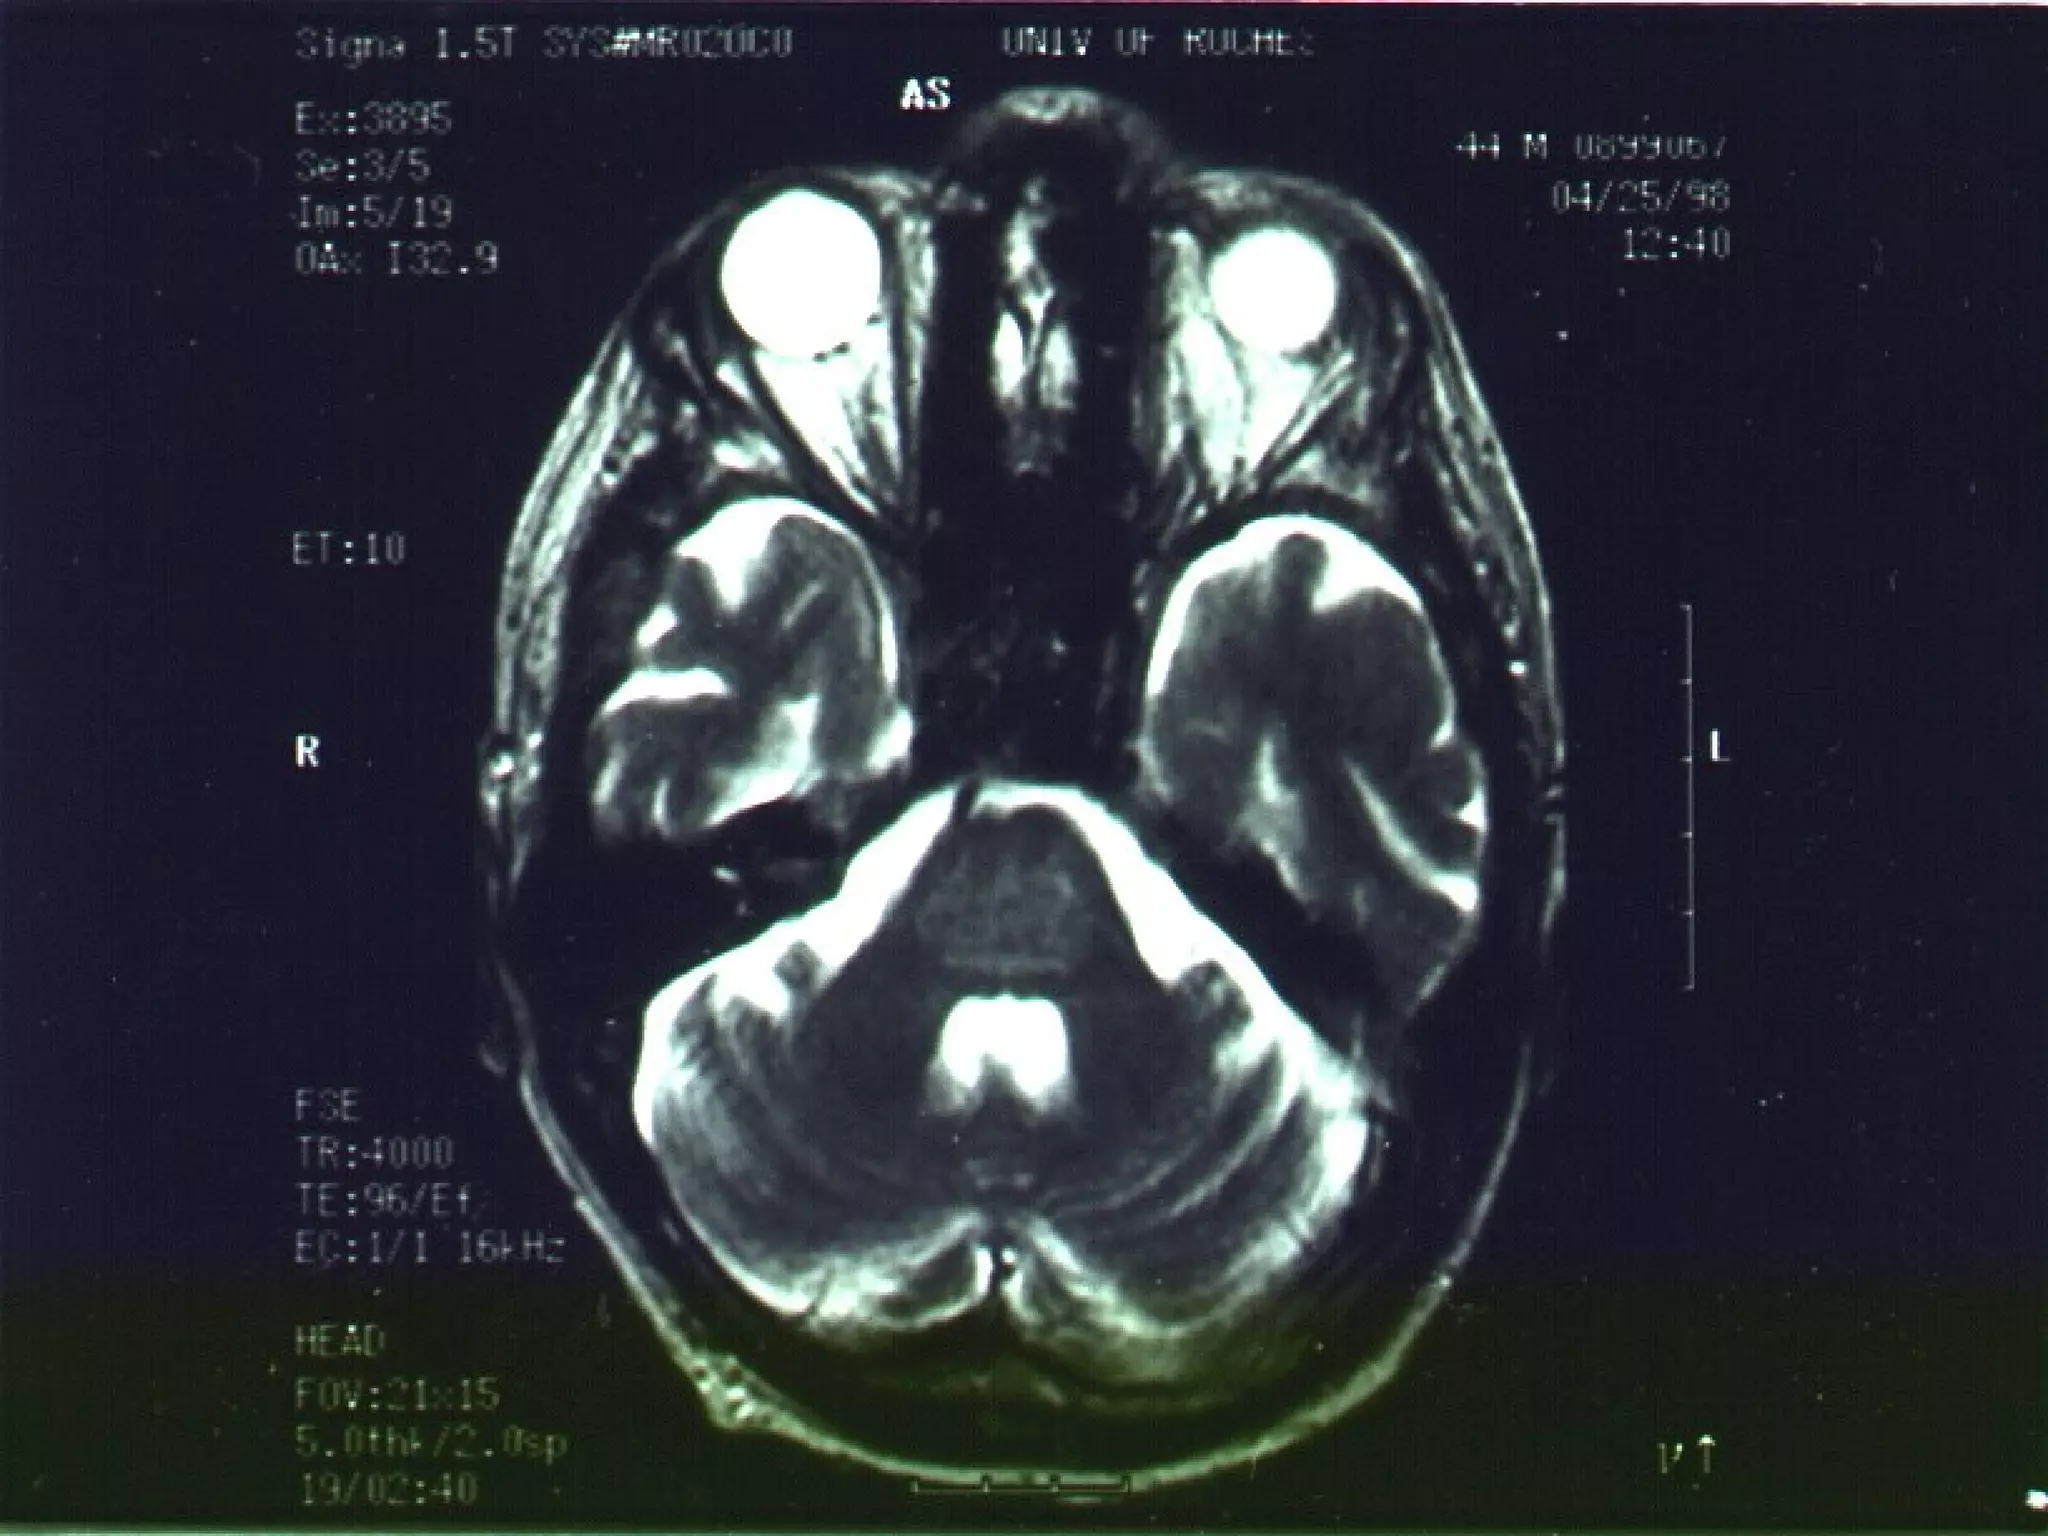

Osmotic Demyelination SyndromeOsmotic Demyelination Syndrome

Within one to several days central demyelinatingWithin one to several days central demyelinating

lesions may occur, particularly in the ponslesions may occur, particularly in the pons

(central pontine myelinolysis or CPM)(central pontine myelinolysis or CPM)

• Symptoms: dysarthria, cranial nerve palsies,Symptoms: dysarthria, cranial nerve palsies,

quadriparesis, coma, “locked-in” syndromequadriparesis, coma, “locked-in” syndrome

– Often irreversibleOften irreversible

• Risk of CPM low if [NaRisk of CPM low if [Na++

] raised by < 0.5 mmol/hr] raised by < 0.5 mmol/hr

or <10-12 mmol/l in 24 hrsor <10-12 mmol/l in 24 hrs